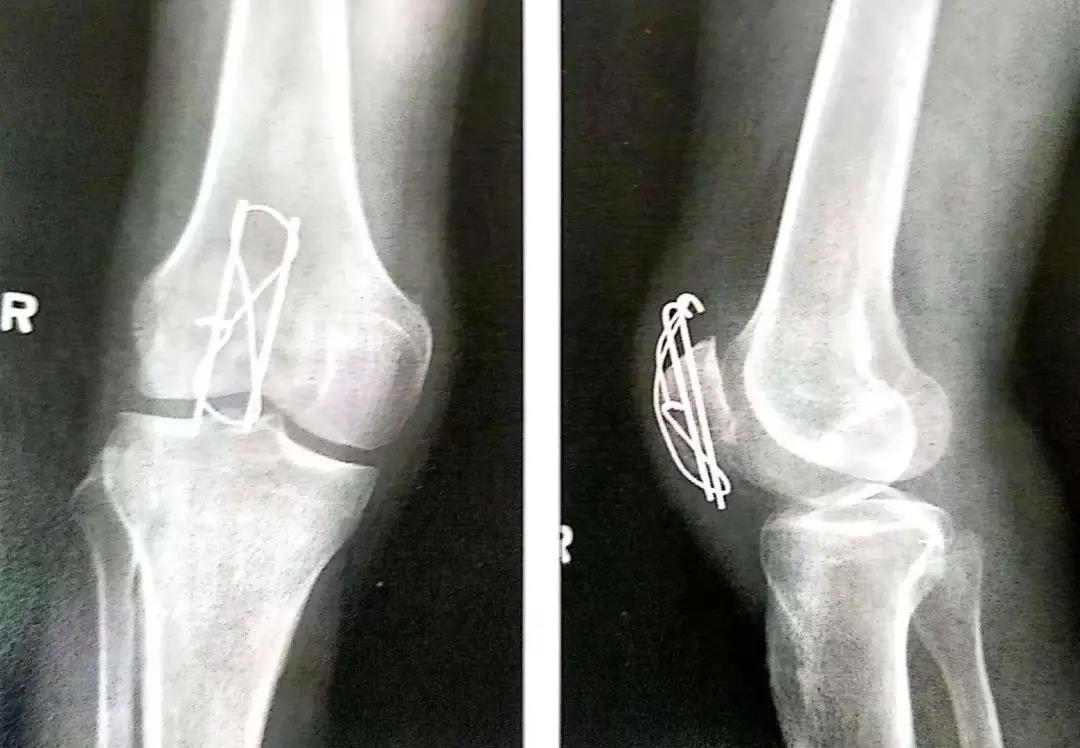

- 使用14或16号的导管作为环扎线的通道。将其穿过临近骨质的四头肌腱和髌韧带内以尽量减少由钢丝所致的软组织损伤。钢丝尽可能接近髌骨,这一点很重要。

- 然后以导管作为通道将18号钢丝穿入软组织内。

- 钢丝的两端在髌骨前面呈8字形交叉。张力带也可打成非交叉的方式。

- 如果复位满意,用老虎钳在两边慢慢拧紧钢丝。

- 8字形钢丝的内外两边要交替拧紧以使横过骨折端的张力均衡。

- 单侧拧紧会导致不均衡压力,并使环另一边的过度松弛无法恢复。

- 钢丝拧得过紧会导致骨折再次移位或者使骨折进一步加重。

- 两平行克氏针的末端剪断后在张力环上翻转180°,上下两端埋入骨内以防止其移位。